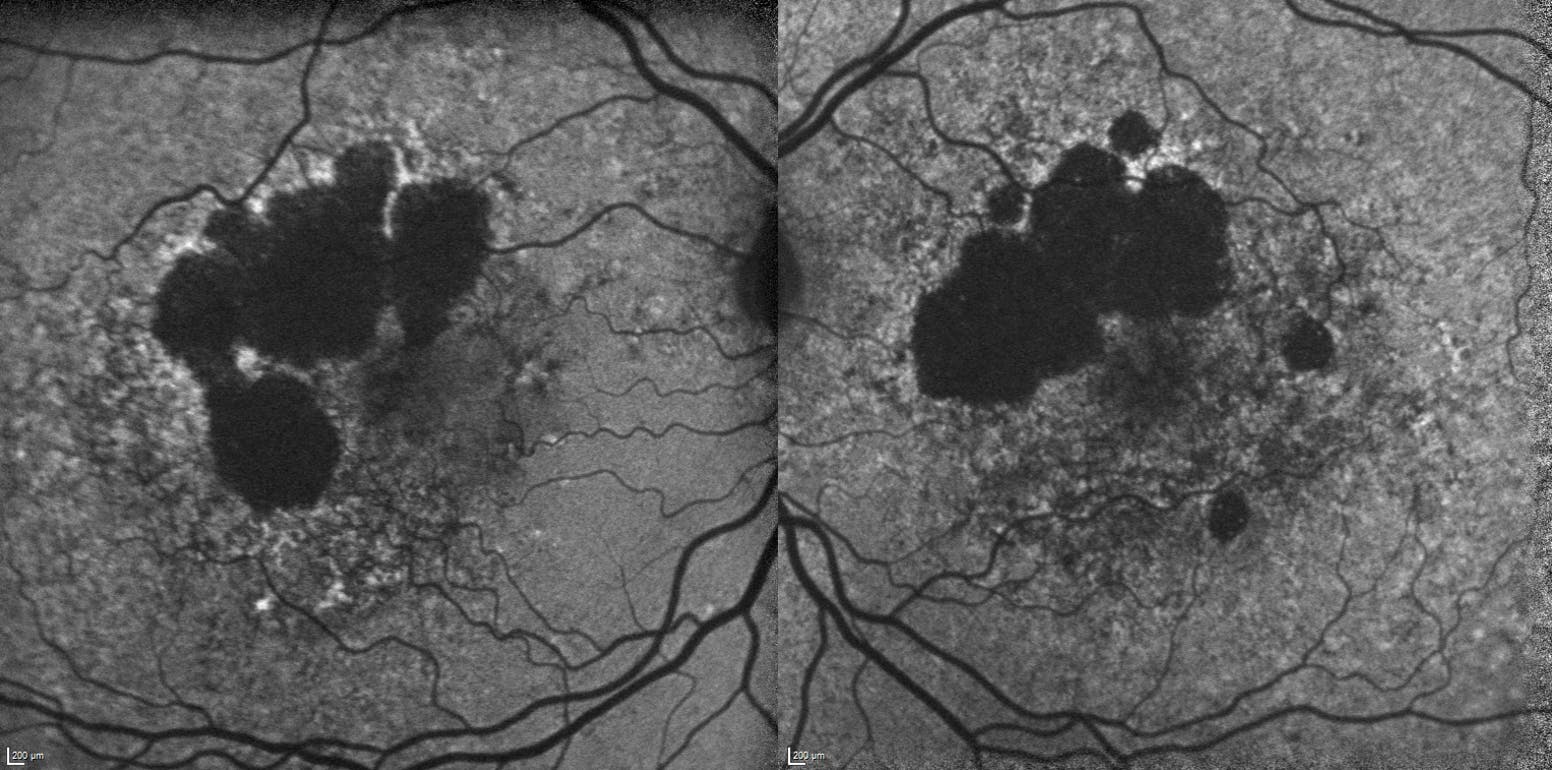

<p>Figure. FAF shows bilateral GA with partial foveal involvement.</p>

Figure. FAF shows bilateral GA with partial foveal involvement.

Imaging tools such as OCT and fundus autofluorescence (FAF) are an important adjunct to the clinical exam. With OCT, I can evaluate macular topography and drusen characteristics, assess the presence of iRORA or complete RPE and outer retinal atrophy (cRORA), and characterize PEDs. FAF is used extensively to follow GA progression and foveal involvement, and to evaluate the macula surrounding the GA lesions. These imaging modalities provide longitudinal structural data, support early detection of atrophic changes, and allow retina specialists to compare images across visits (Figure).